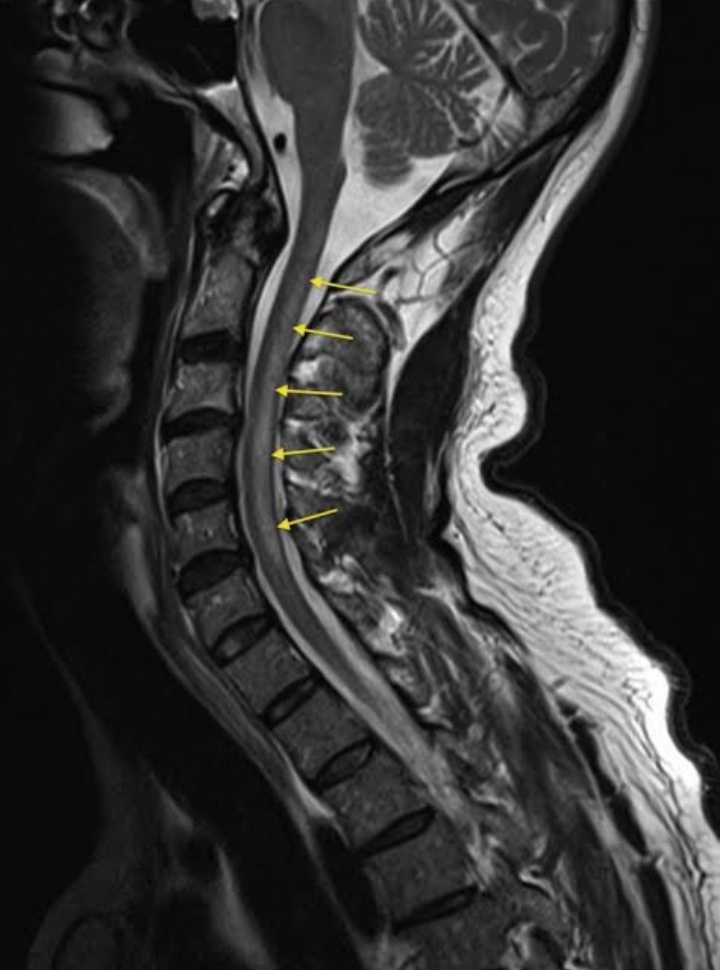

Subacute Combined Degeneration of Spinal Cord - The Only Manifestation in an Otherwise “Normal” Vitamin B12 Deficient Patient

Dr Darshankumar Manubhai Raval, MD, Nritya Brijesh Trivedi, Shraddha Trivedi, Yash Vaghasiya, Aditi Parida

International Journal of Innovative Research in Medical Science·August 30, 2022